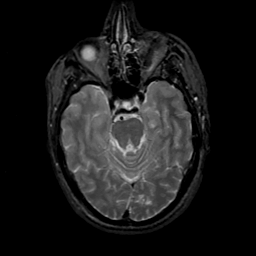

MR Study #18, July 21, 1991 -- Slice #17

[Home][Help][Clinical][Tour 1][Tour 2] Slice 17